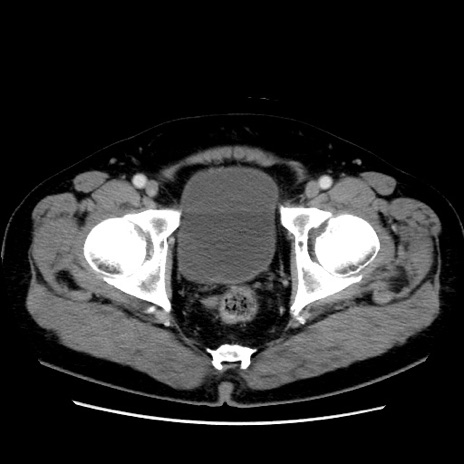

症例16(横断像)

【症例】 70歳代男性

【主訴】 腹痛、嘔吐

【現病歴】 約1ヶ月前より間欠的に腹痛と嘔吐あり、当院消化器内科を受診したところCTで多発する肝臓のLDAを指摘され、精査中であった。以降は消化器症状は安定していたが、2日前より嘔気と腹痛があり、同日より排便・排ガスが消失した。改善認めず、 本日、救急外来を受診した。

【既往歴】 大腸ポリープ切除後。

【身体所見】意識清明・会話良好、BT 36.3℃、BP 127/80mmHg、 P 80bpm、腹部:膨満あり、平坦・軟、上腹部正中および下腹部正中に圧痛あり、反跳痛なし、筋性防御なし。

【データ】WBC 7200、CRP 0.77